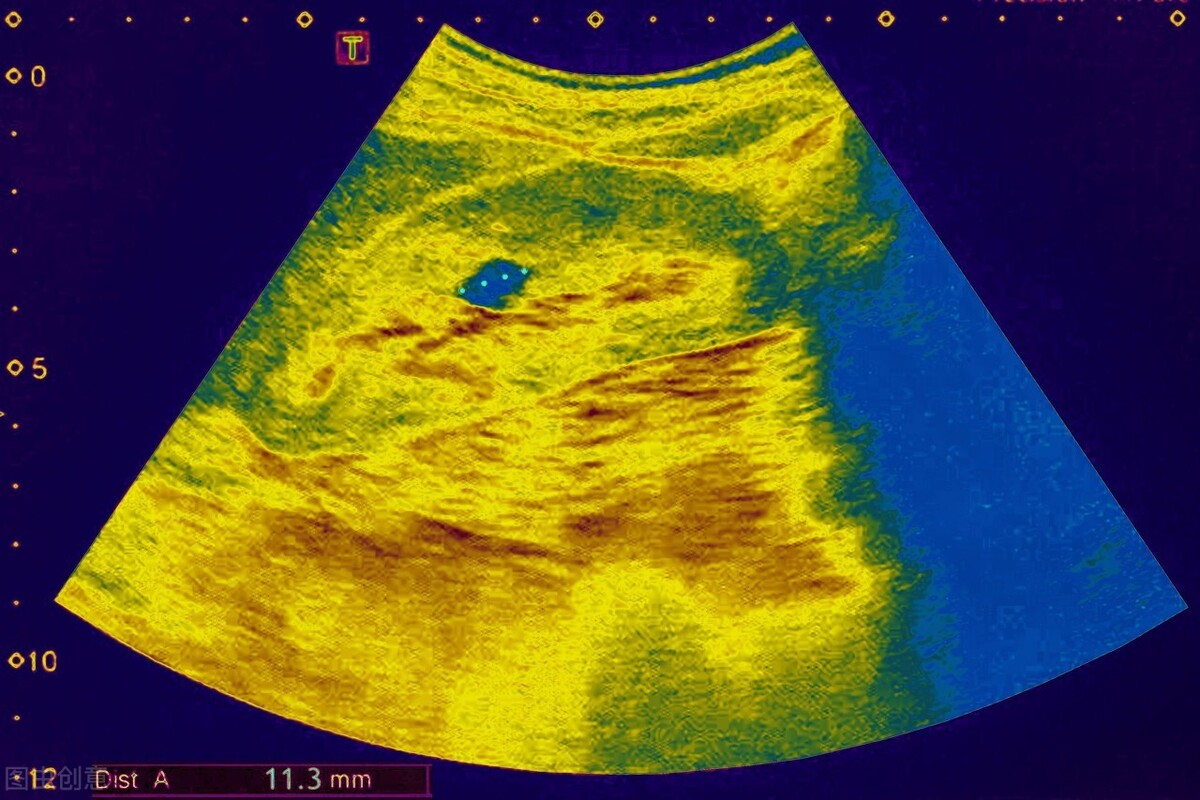

有些朋友,体检时看到超声报告单上说有肾囊肿,就担心的不行。

其实,不要紧张,肾囊肿是一种临床上常见的一种肾脏囊性病变,一般不伴有肾功能减退,年龄越大,其发生率越高,囊肿数量也可随年龄增长而增加。

l 囊肿监测:应每年复查1~2次肾脏超声,监测囊肿大小,如囊肿生长较快,必要时应进行干预治疗。